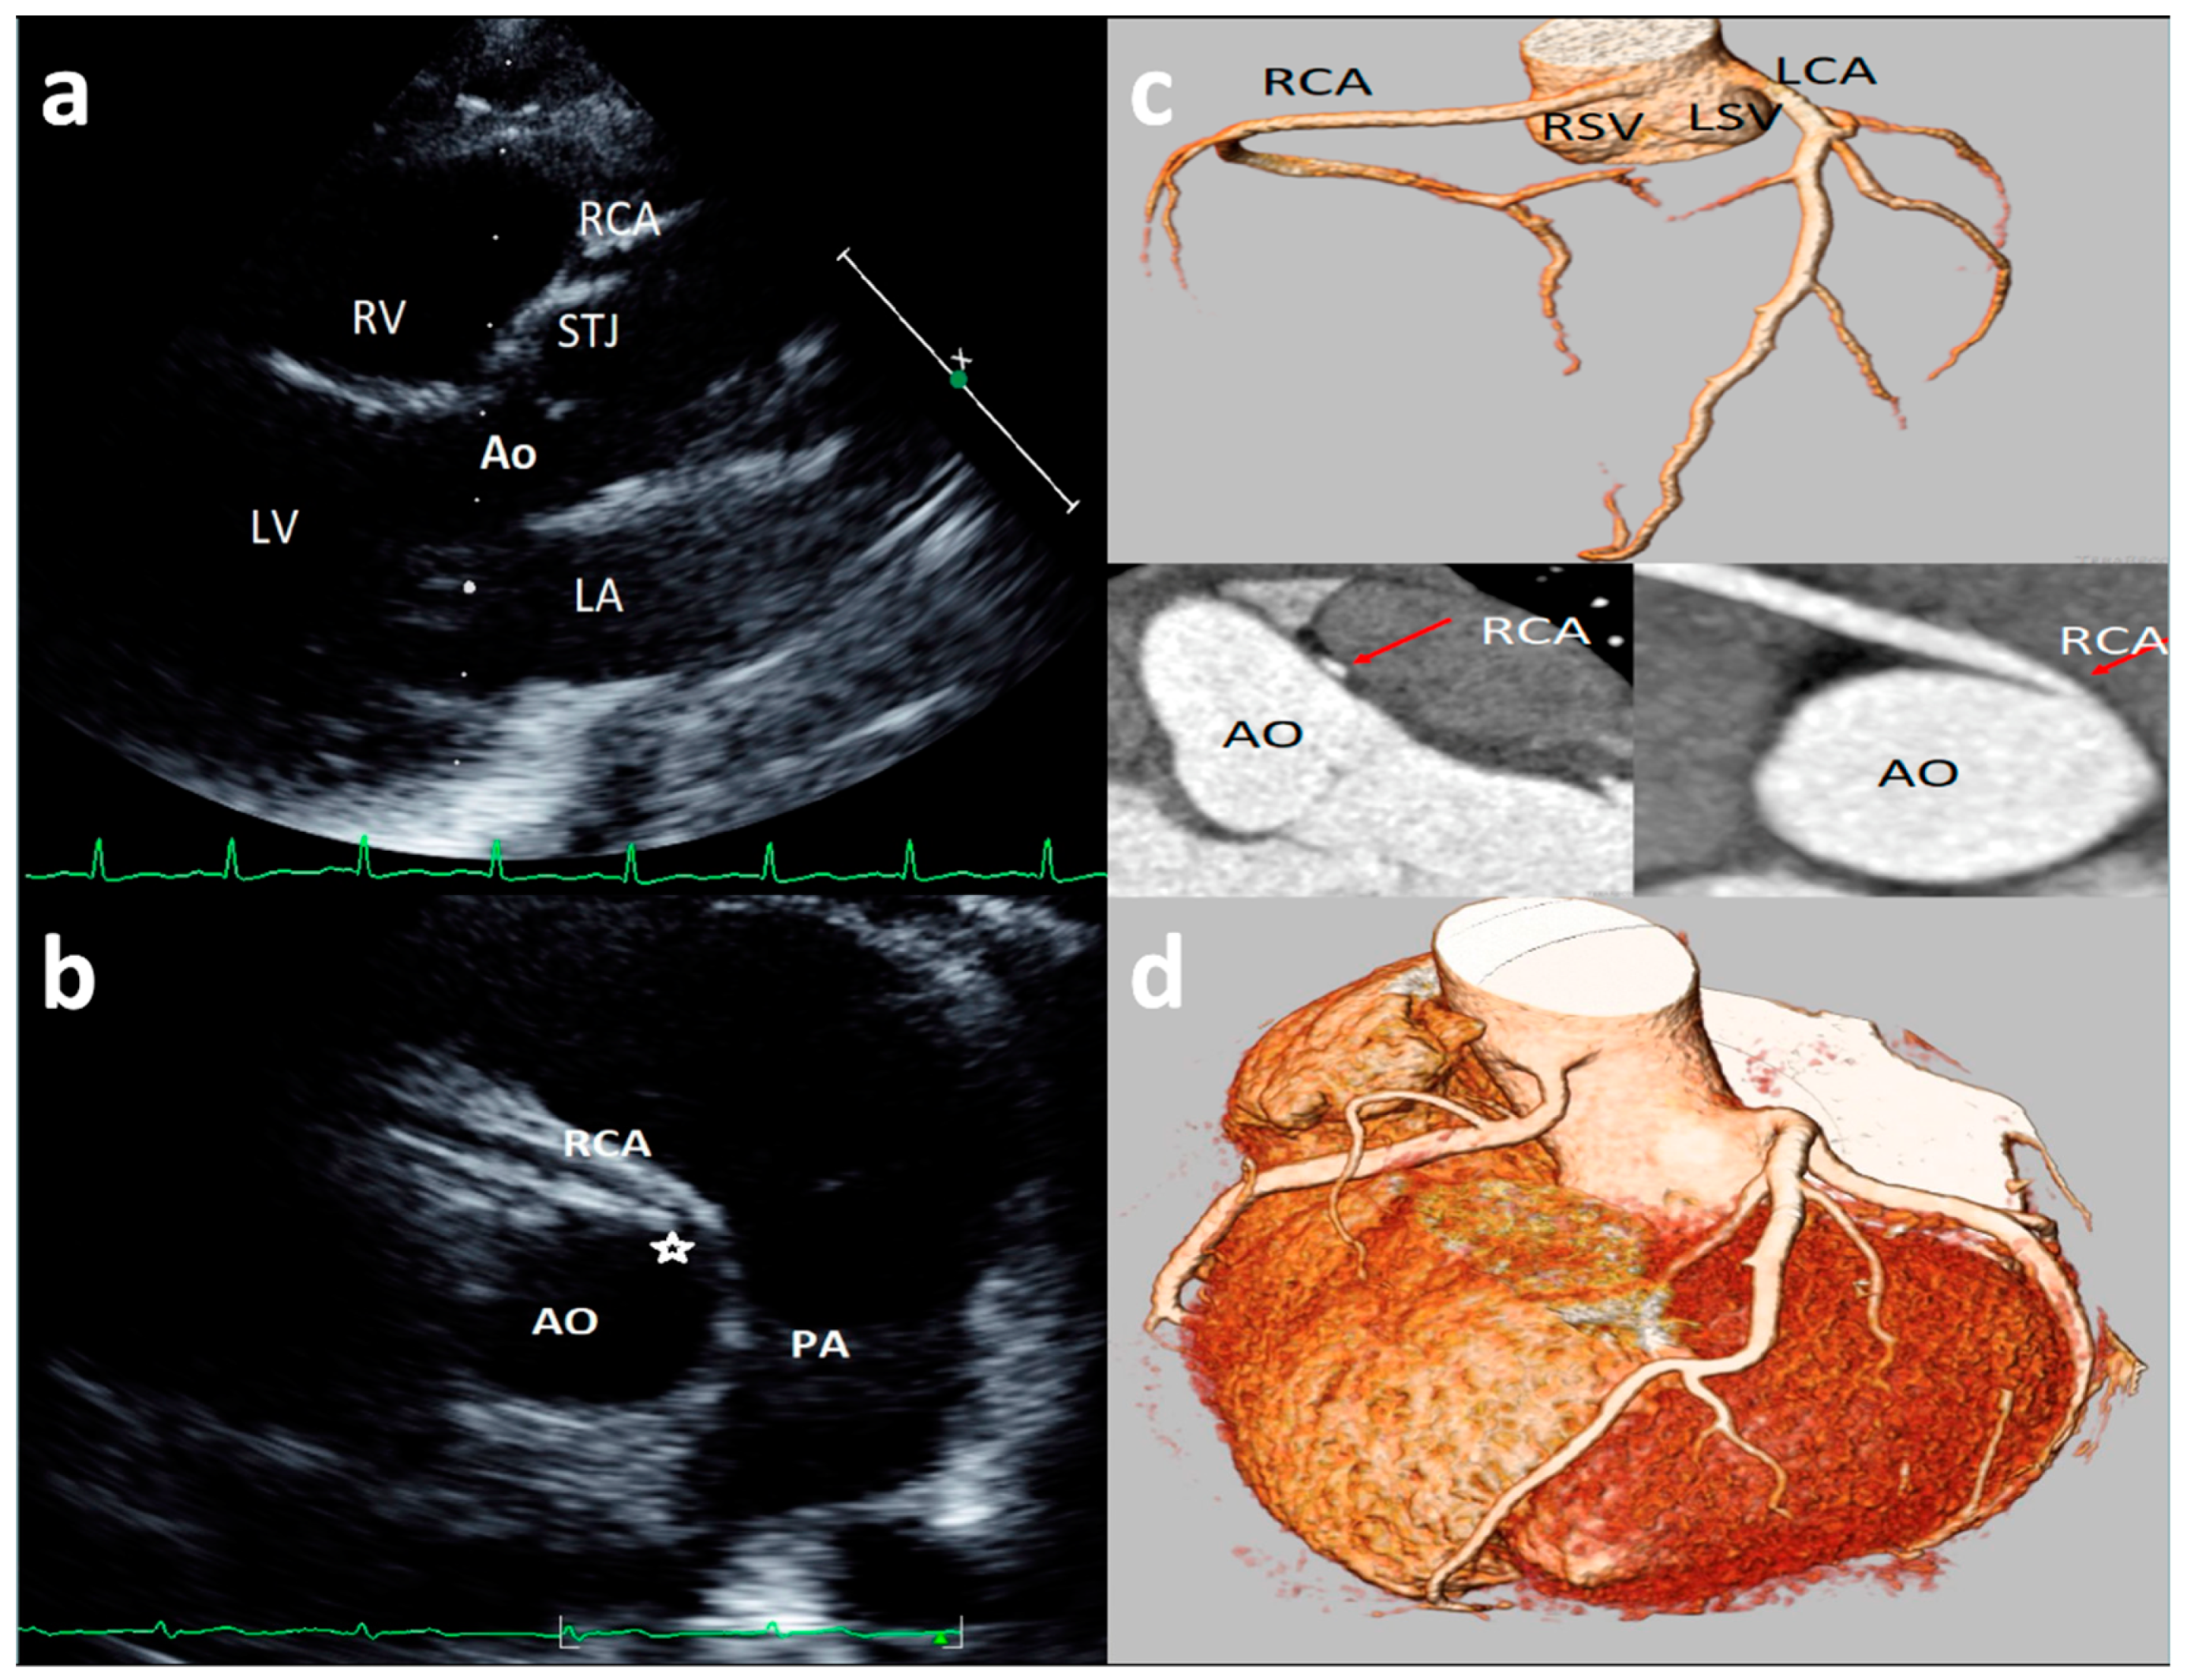

Figure 3. Asymptomatic 17-year-old boy evaluated for the presence of two premature ventricular beats at peak of stress test in routine preparticipation evaluation for sports competition. Parasternal long-axis view showing right coronary artery (RCA) high take-off coronary artery above the sinus of Valsalva (a). The acute angulation origin is clearly visualized in short-axis view (b) and was confirmed at CT (c). After CT confirmation of the defect, a myocardial scintigraphy was performed revealing a small ischemia (8%) in the RCA territory at peak. We advised sport restriction. Ao = aorta, LCA = left common coronary artery, RCA = right coronary artery, LSV = left sinus of Valsalva, RSV = right sinus of Valsalva. (d) is an example of 73-year-old man showing symptoms of dyspnea. 3D-Volume Rendering CCTA showing the right dominant coronary artery (RCA) high take-off two centimeters distal to the sinutubular junction at the level of the anterior ascending aortic wall.

3.6. Coronary Artery High Take-Off

High take-off coronary artery is a rare anomaly [33,34,35,36,37,38,39,40,41,42,43] that may present in isolation or associated with other congenital cardiac malformations [35,36,37,38,39,40,41,42,43], mainly identified for the RCAs (up to 84.46% of cases) [33]. There is still limited literature on the visualization and definition of RCA high take-off by echocardiography [13,14,23]; although there is not a consensus on the definition of high take-off by echocardiography, all the studies included in the present review defined high take-off as an origin above or distal to the sinutubular junction (STJ) [13,14,23]. An example of high take-off of RCA from our case series is reported in Figure 3. A very recent [13] study, of 1045 consecutive elite adolescent football players, identified coronary high take-off origin in 13 subjects (i.e., 1.14%). Eccentric RCA origin with a high take-off and partial intra-arterial course was observed in two cases (with no slit-like ostium and no intramural course); high take-off origin of the RCA with acute angle was observed in one case; high take-off of the RCA origin (with no intramural or slit-like orifice) was observed in 11 cases. Of the latter 11 cases, diagnosis was feasible only from the parasternal long-axis view, where the ostium of the RCA was measured from 2.3 to 6.8 mm above the sinutubular junction [13]. Lytrivi et al. [24] documented RCA high take-off in 53 cases (0.36%), LCA high take-off in four cases, and high take-off of both the coronary arteries in two cases of a valuable cohort of 14,546 pediatric subjects [23].